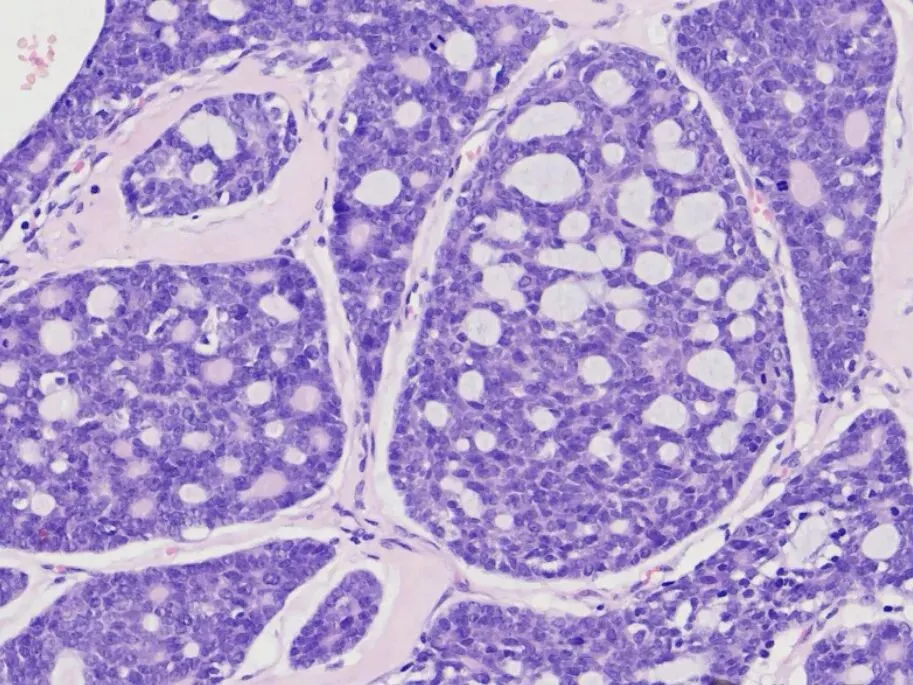

3.镜下:

①肿瘤细胞由腺上皮细胞和肌上皮细胞构成。两种细胞均较小,核深染,胞质稀少,核分裂象少见。腺上皮细胞排列成管状;肌上皮成分占肿瘤的大部分,常为片状或围绕在管状结构外围,细胞核常呈角状。

②按肿瘤排列可分为3种类型,分别为筛状型、管状型、实体型。同一肿瘤中可见上述3种结构。

③肿瘤细胞常浸润神经纤维